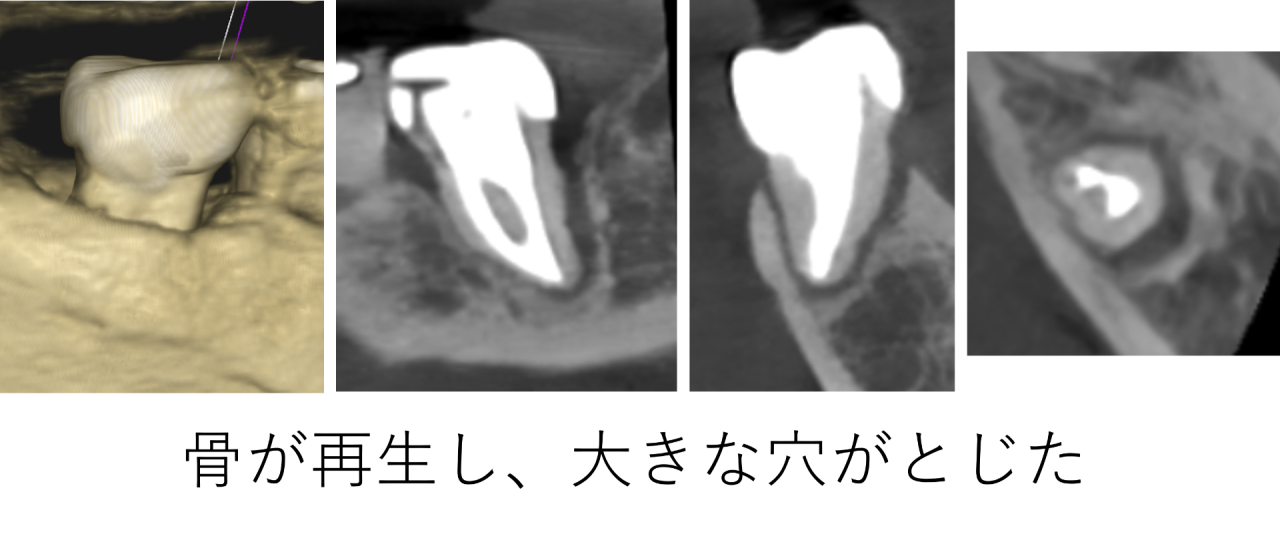

治療後は経過観察を行いました。1年経過し、患者様は引き続き痛みもなく食事ができているとのことで、CTを撮影しました。すると、溶けていた骨はほとんど再生しており、大きな穴は完全にふさがって(とじて)いました。